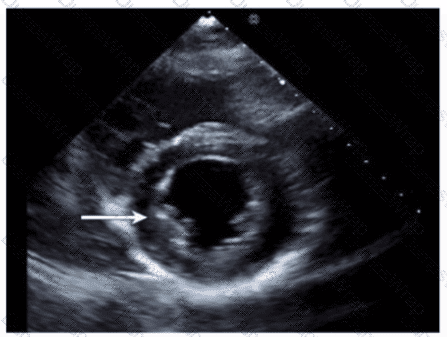

Which finding is demonstrated in this video?

Options:

Bioprosthetic valve replacement

Mechanical valve replacement

Annuloplasty ring repair

Native valve with extensive calcification

Answer:

CExplanation:

The echocardiographic video shows a prosthetic ring-like structure attached to the mitral annulus with preserved native leaflet motion, consistent with an annuloplasty ring repair. Annuloplasty rings are used to reduce the mitral annulus size and improve leaflet coaptation in mitral regurgitation without replacing the valve.

Bioprosthetic or mechanical valve replacements would show distinctly different echogenic valve structures with leaflet or disc motion replacing the native valve. Extensive calcification of a native valve appears as echogenic, thickened leaflets without a discrete ring.

This is described in the "Textbook of Clinical Echocardiography, 6e", Chapter on Mitral Valve Repair Techniques【20:400-405†Textbook of Clinical Echocardiography】.